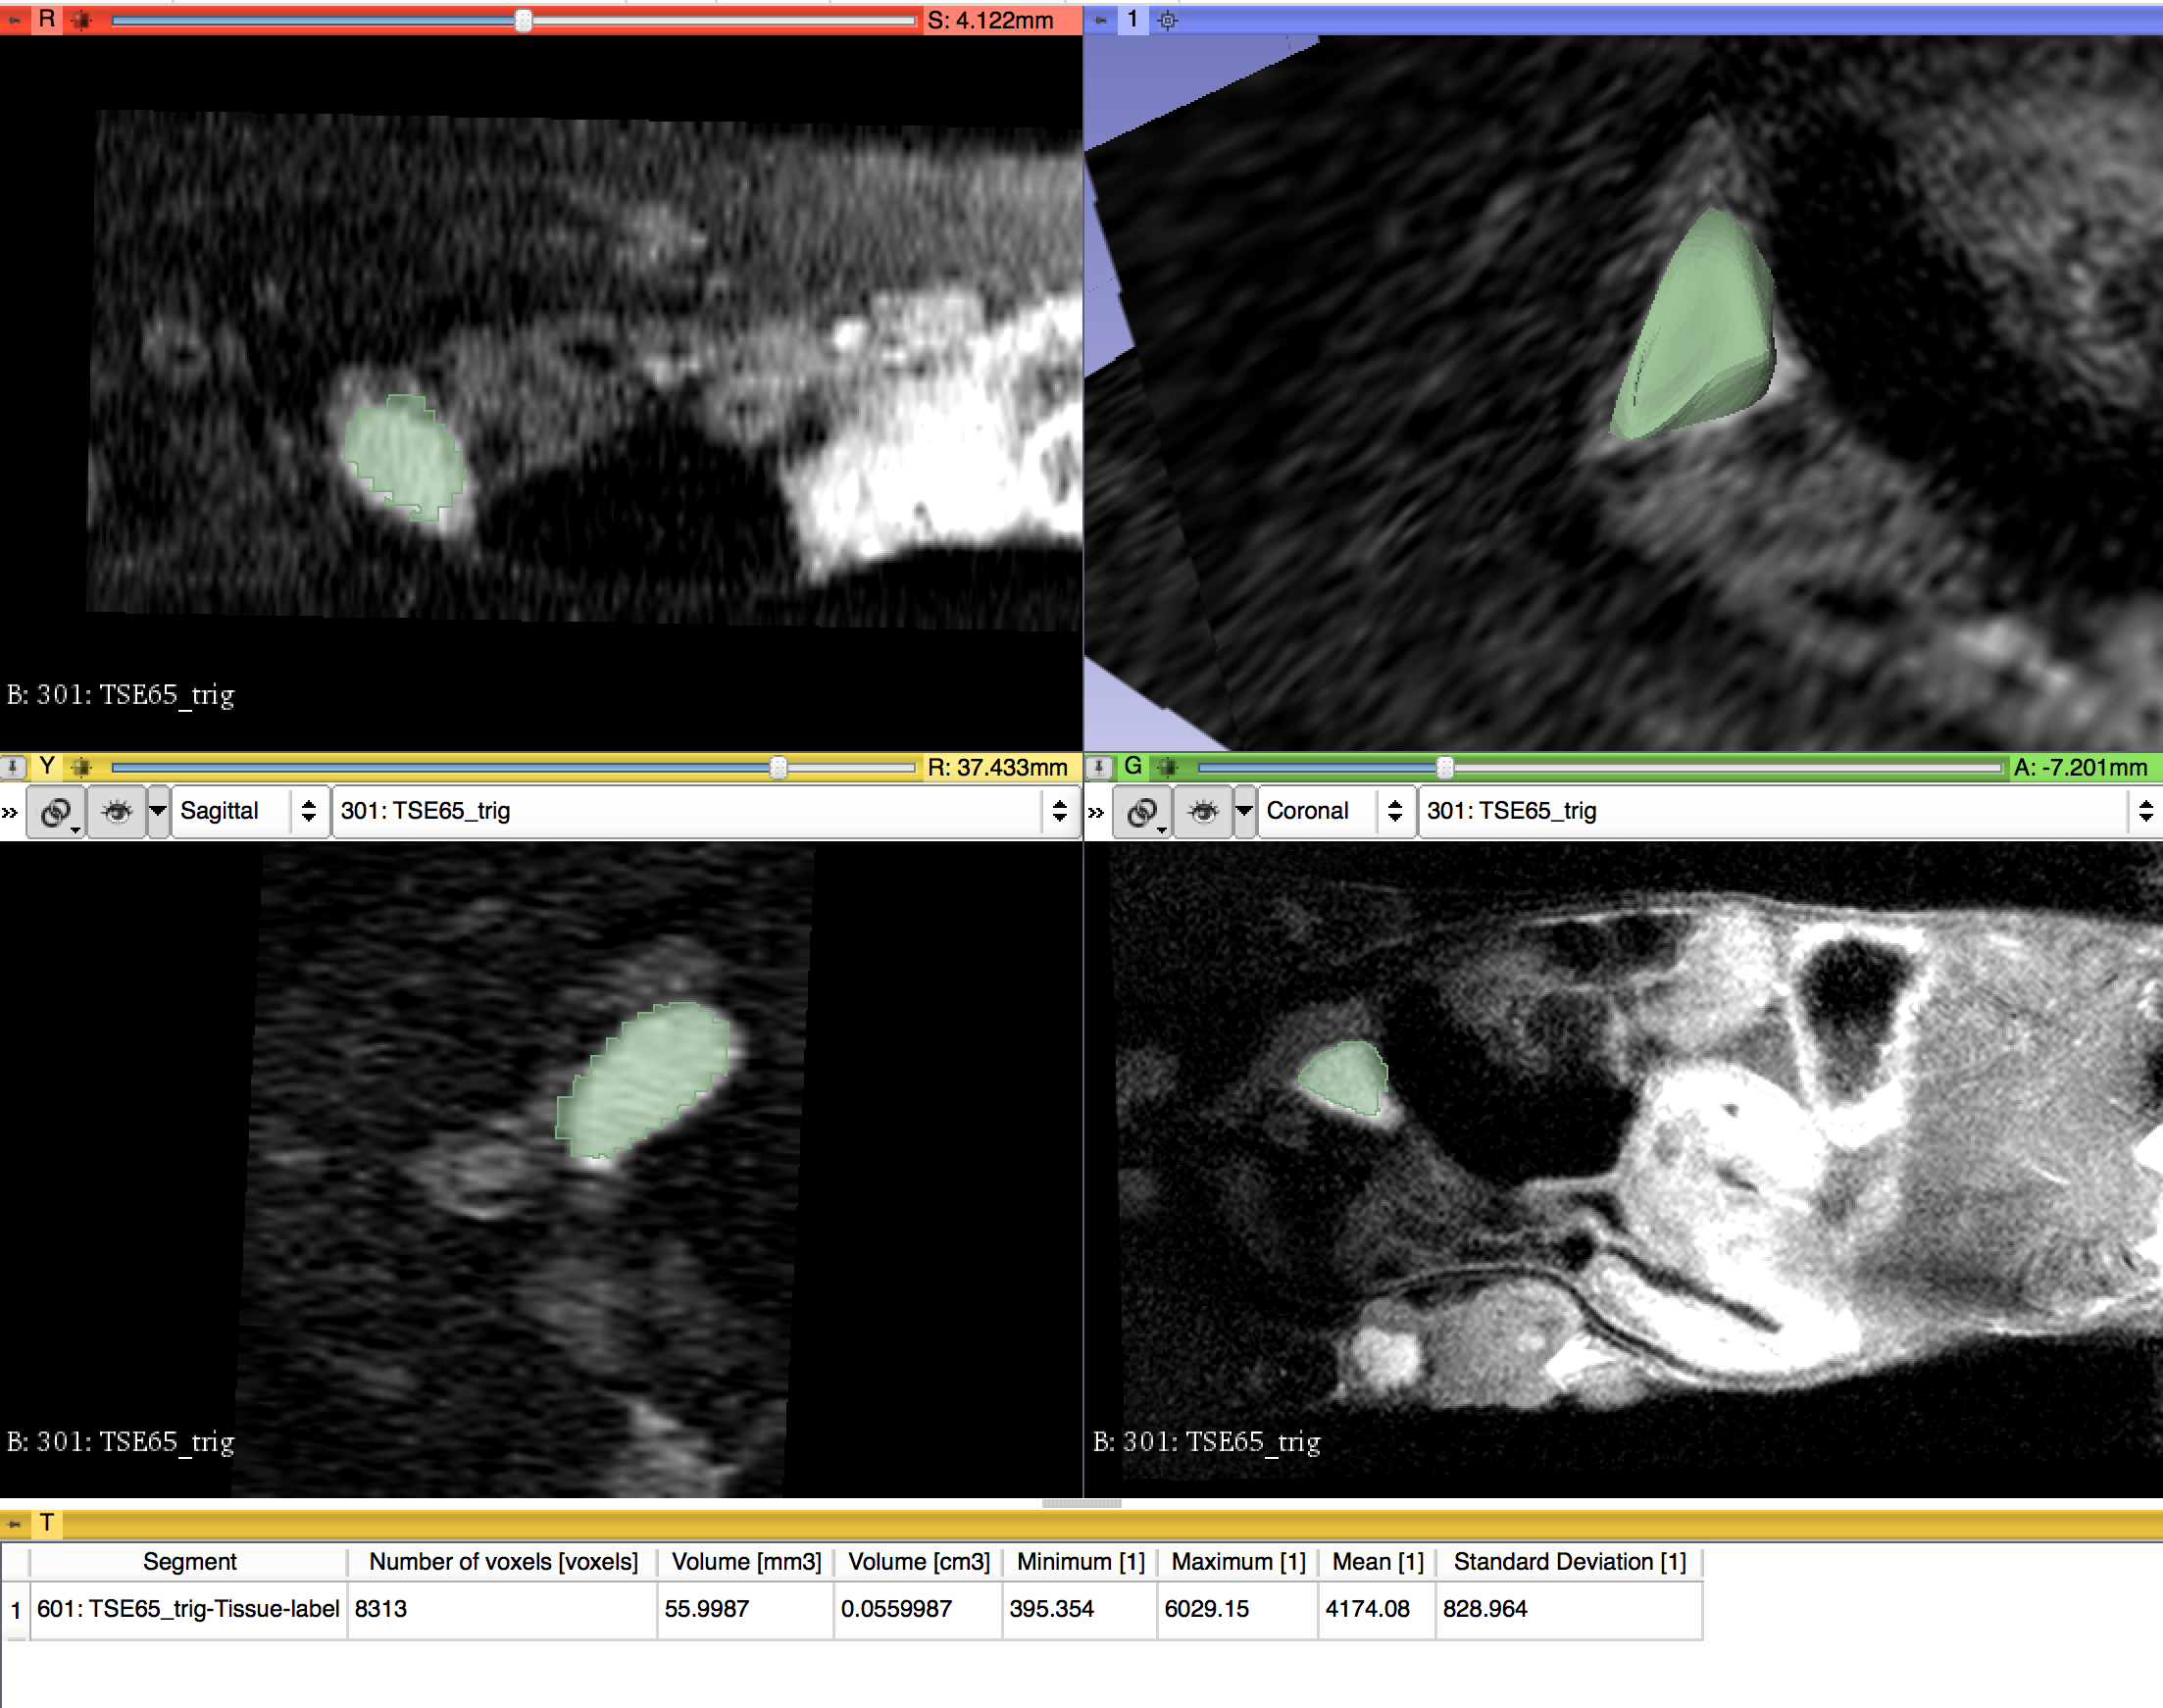

For this project, we aim to bring small animal MR datasets in DICOM format and repeat the process developed for the

QIICR program to segment a lesion (a Neuroendocrine Tumor in this case), convert the segmentation to a DICOM segmentation

using the DCMQI slicer extension, and finally measure the segmentation using the Quantitative Reporting module. Our aim

is to develop a set of repeatable analysis steps we can put into place to analyze additional datasets in our lab.

- Segment lesion using Slicer Segmentation Wizard

- Reprocessed successfully and measured DICOM segmentation object using Quantitative Reporting module